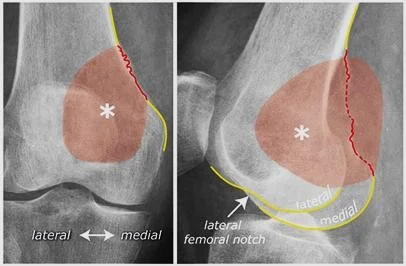

Patient â 40âyearâold female

Mechanism â Jumped from the 2nd floor

Presentation â Pain and swelling around the right knee

Site â Lateral tibial plateau

Type â Simple

Fracture line â Vertical split

Intraâarticular â Yes

Displacements â Small gap in the articular surface

Special issues â Requires surgery for absolute stability

A 32âyearâold patient fell from a palm tree and now presents with pain and swelling around the left knee.

- Site: Lateral tibial plateau

- Fracture type: Comminuted

- Fracture line: Vertical split

- Displacement: Depressed

- Special issues: CT scan required for detailed assessment

- Management needed: Surgical intervention